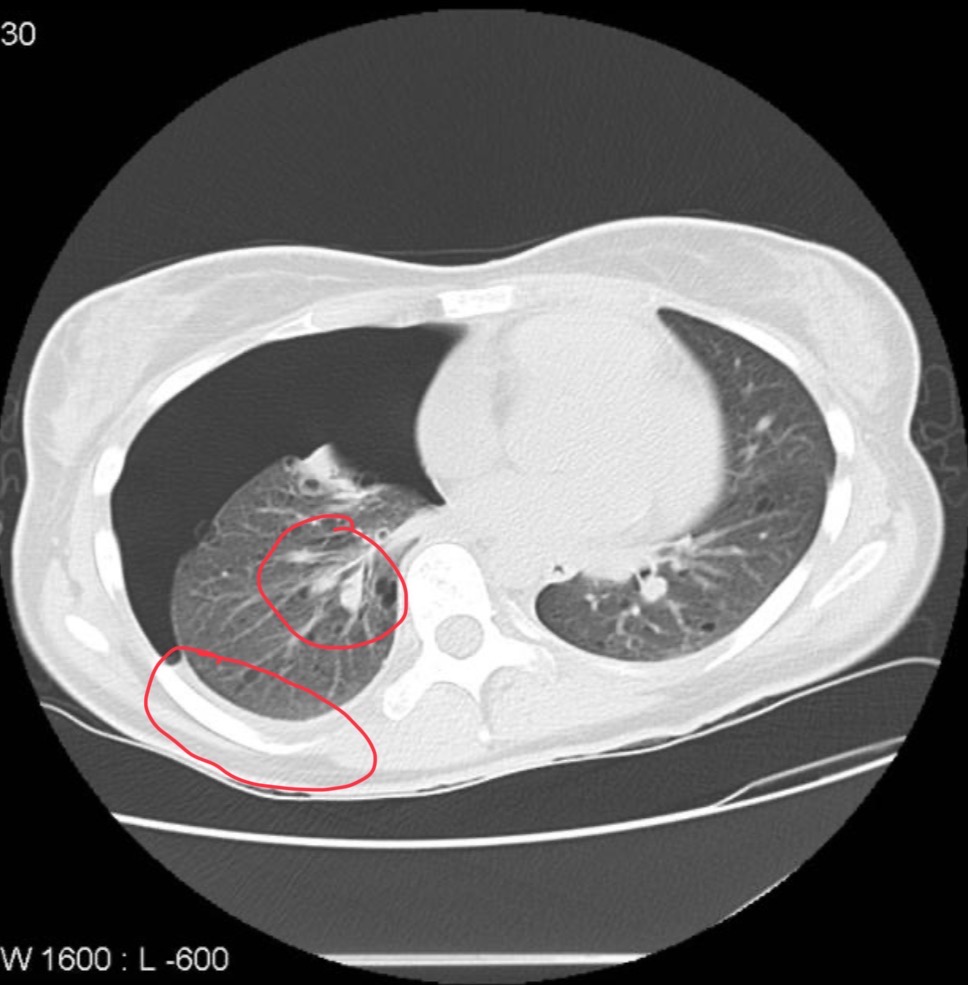

CT of pt

Shows pneumothorax in the right lung with mild plural fusion mediastinum push the left multiple mass lesions then the wild air density cyst surrounded by normal lung tissue.

Pt has tuberous sclerosis with lymphangioleiomyomatosis